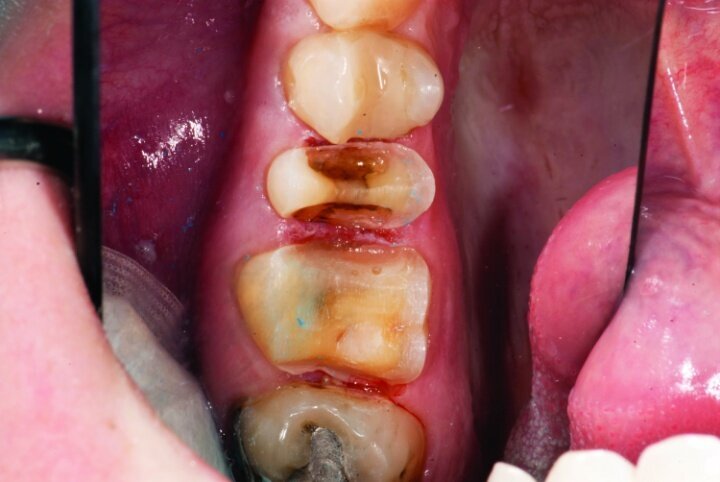

This patient presented for restorations of teeth #3 and #4 (Fig. 1a). Because of the size of the existing restorations, these teeth were diagnosed as structurally compromised (Figs. 1b, c). The prognosis without treatment was fair.

The restorations were to be completed with PlanScan chairside CAD/CAM technology in the same visit.